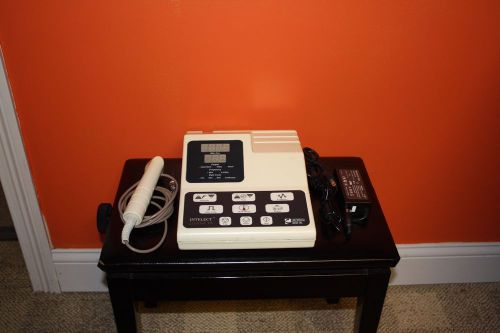

Chattanooga Intelect Legend US Ultrasound w 78047 Applicator Free Shipping!